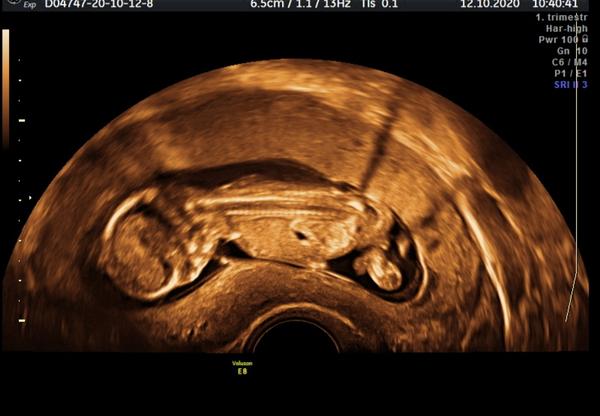

Prohlížím si zrovna fotky z prvního screeningu byla jsem zrovna ve 13 tt. Doktor mi pohlaví zatím říct nechtěl, ale zdá se mi, že na této fotce jde vidět pindik. Nemyslím si, že by to byla pupeční šňůra. Co myslíte vy?

Pidle vsech obrazku co uz tady bylo,by mel kluk hrbolek vic postaveny nahoru..takze za me to kluk nebude hrbolek smeruje spise dopredu...ale je to jen tip dle nekolika obrazku co sem tady videla,ja miminko zatim zadne nemam teprve se snazime...bohuzel uz dlouho takte tady ctu kde co😀

Holka i kluk to v tomto období mají stejně. Rozdíl je jen v úhlu - tak se pohlaví takto brzy určuje. Takže to může to být pořád i holka